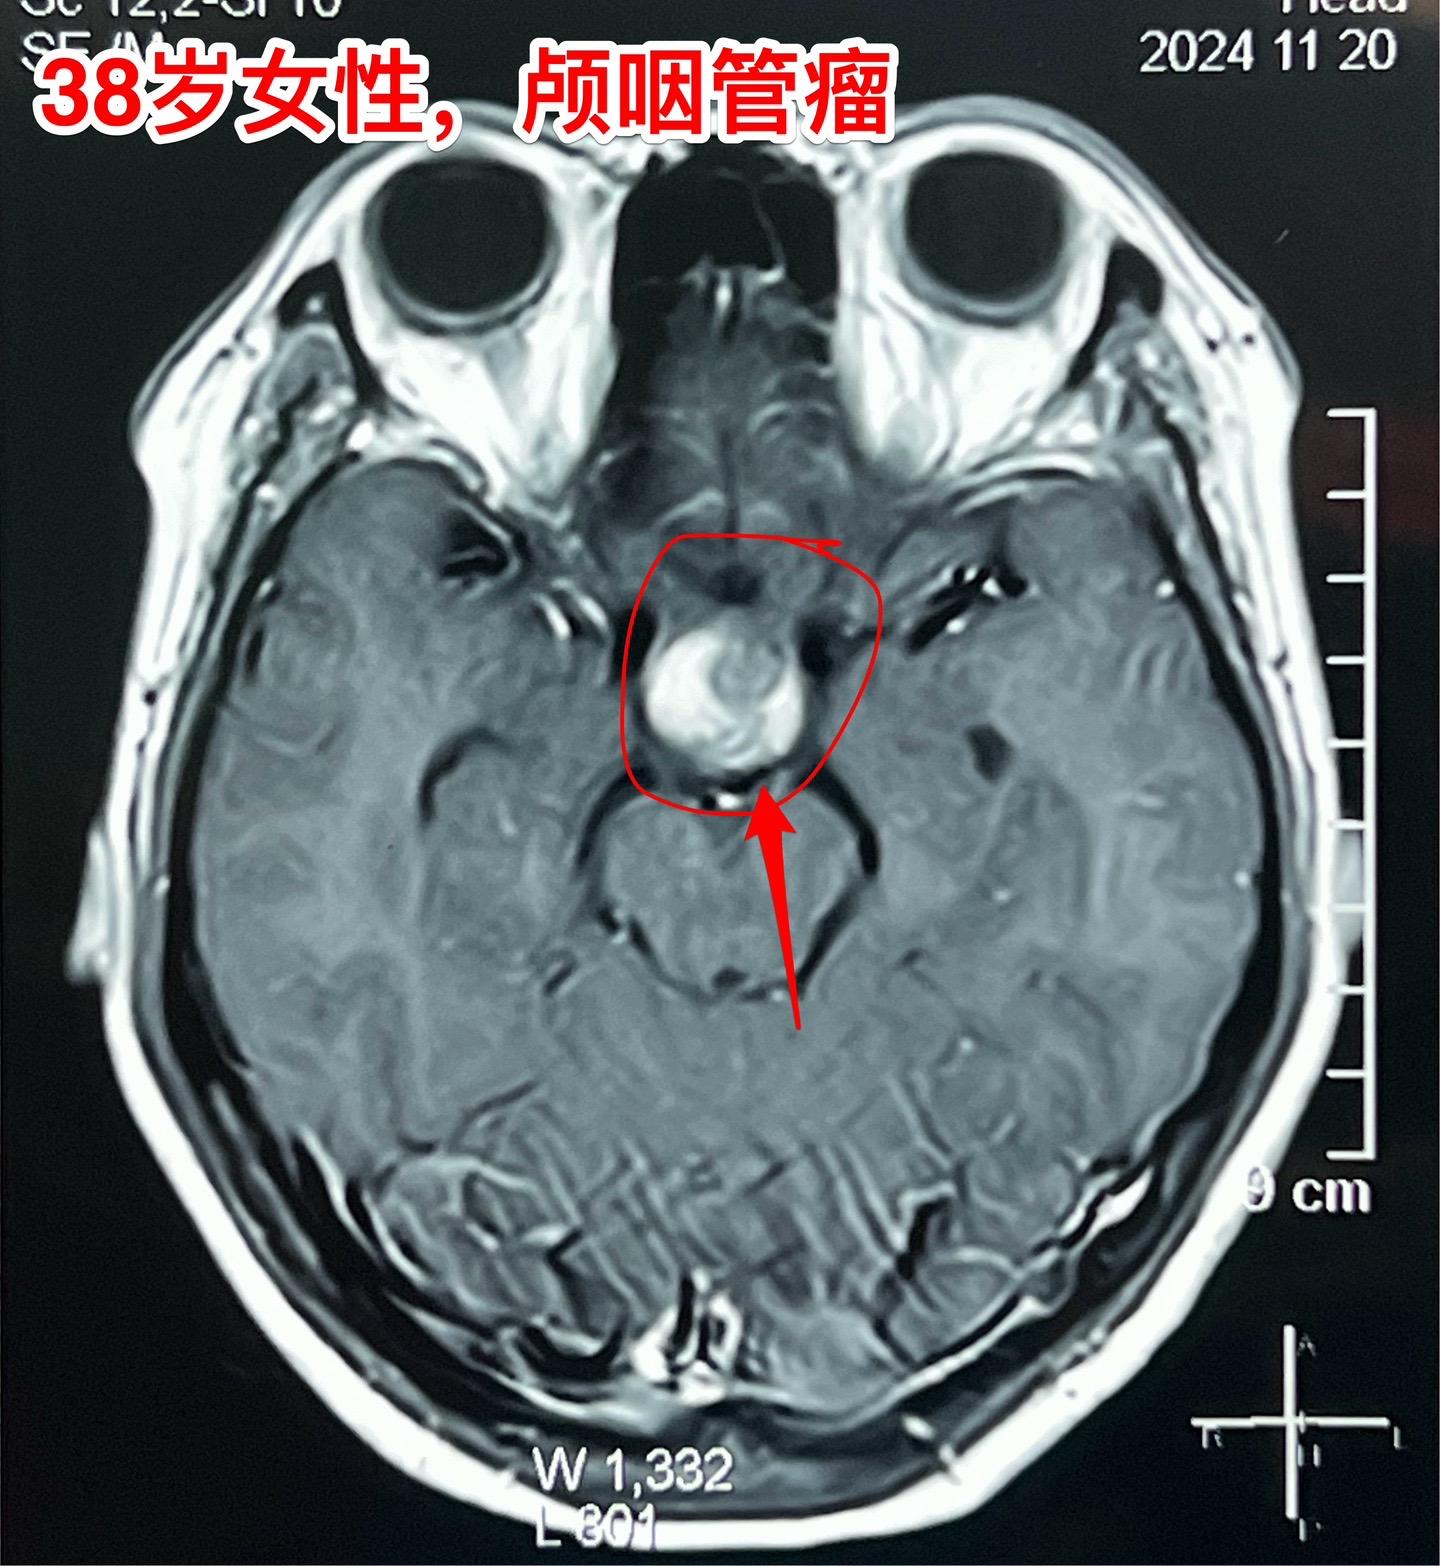

颅咽管瘤等待四年多才作手术,是否合适?偶然发现的颅咽管瘤,病人几乎没有什么症状,是不是要尽早作手术呢?颅咽管瘤的治疗一直是神经外科界的难题,手术时机选择也是一个难点。 今天以一个实际的病人来说明。 38岁的绍兴女性,在2020年初经体检发现了颅咽管瘤,当时几乎没有什么症状,曾经通过咨询过我,之后一直在观察。患者在2014年左右生育孩子,发现颅咽管瘤后内分泌系统都很正常。 直到今年夏天患者发现内分泌系统紊乱了,复查磁共振显示肿瘤体积增大了。她这才下定决心找我